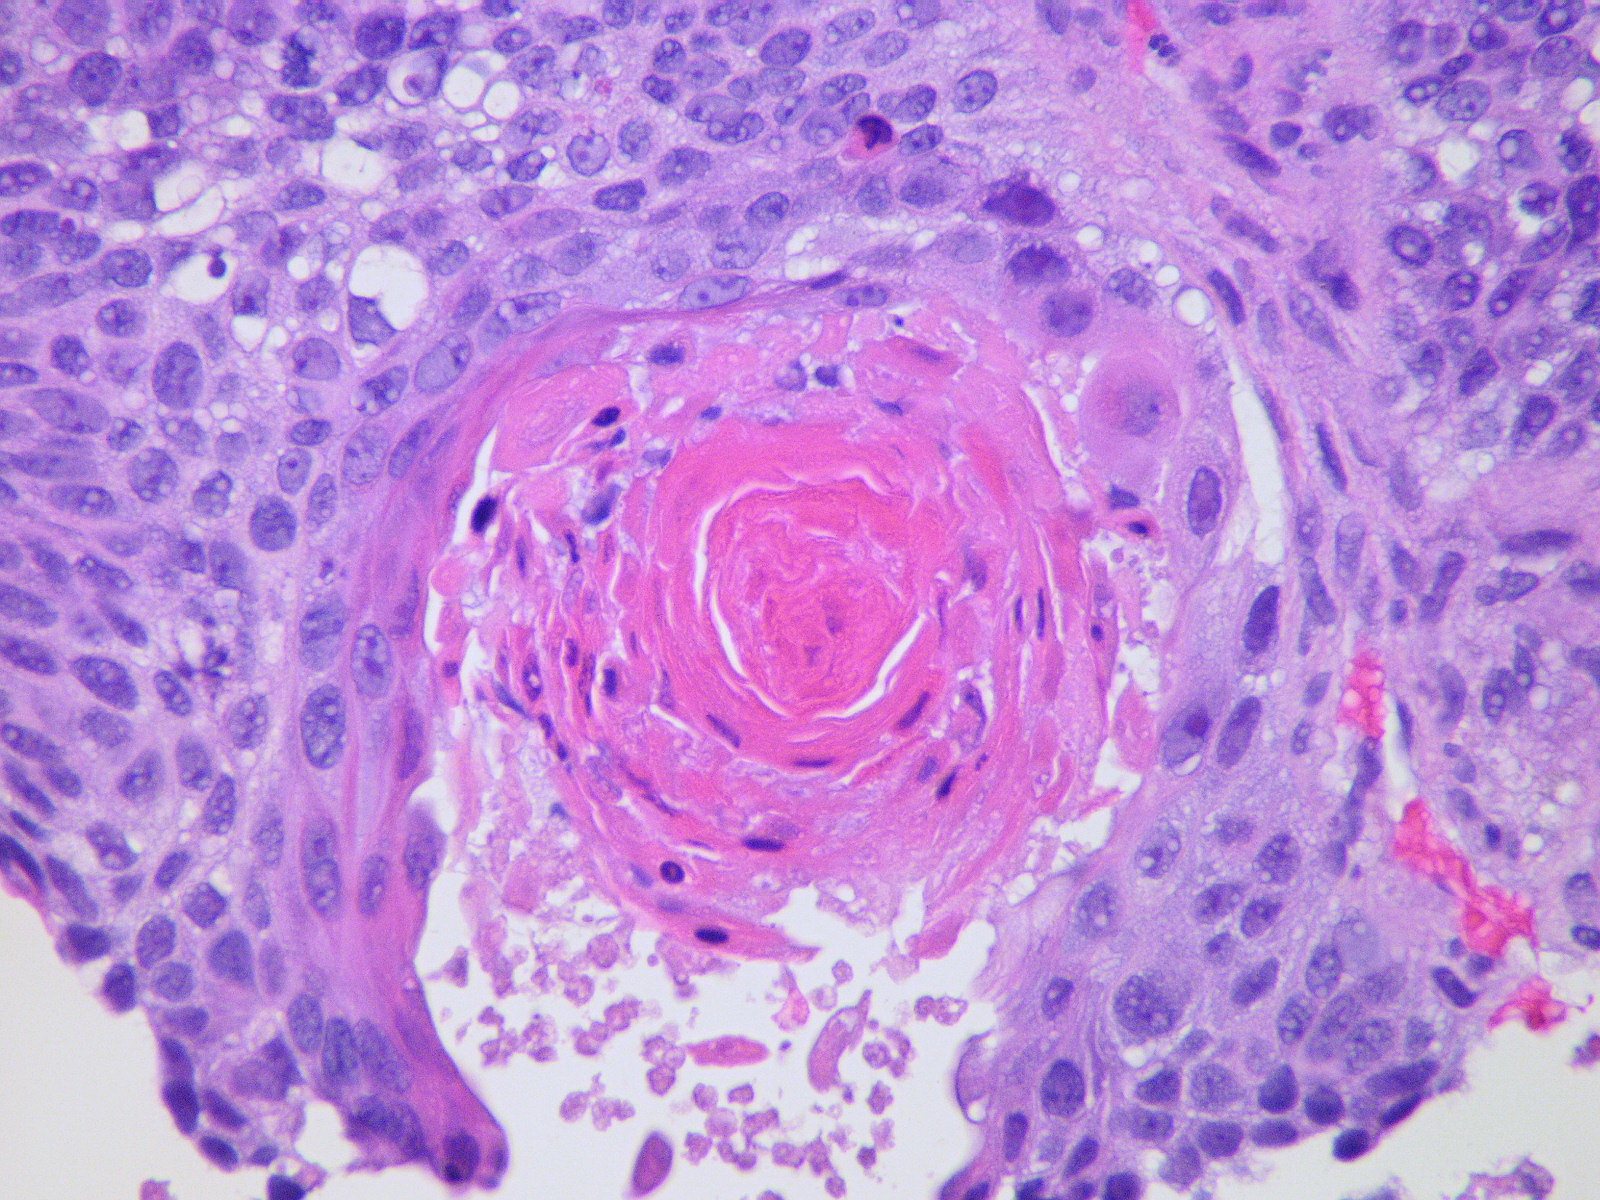

Клетки плоскоклеточного рака